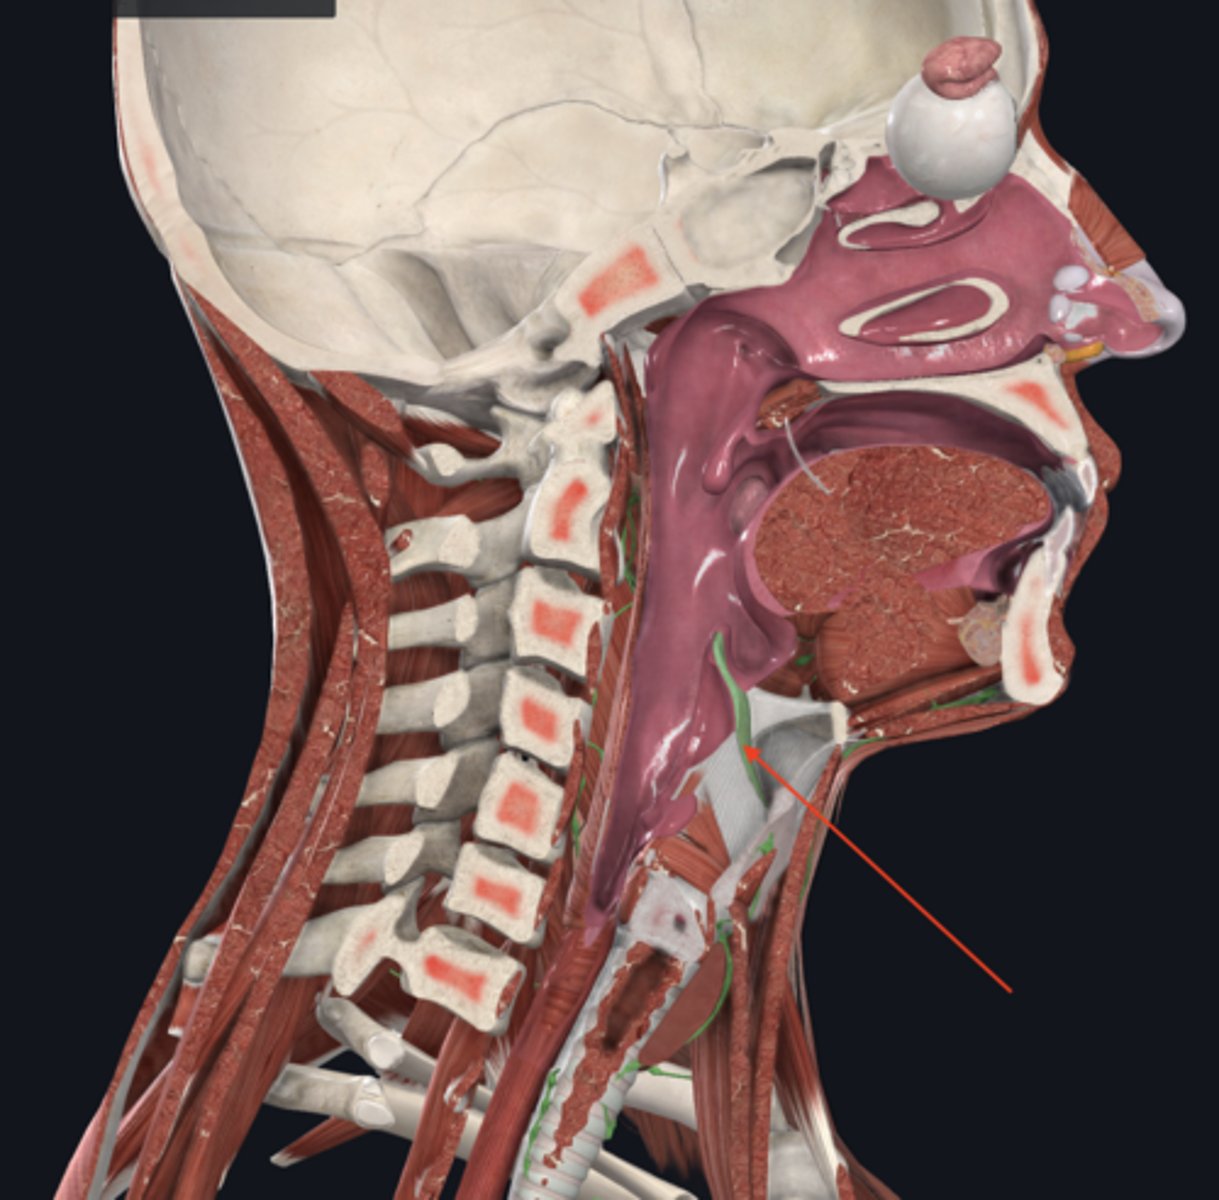

laryngopharynx

name the circled region